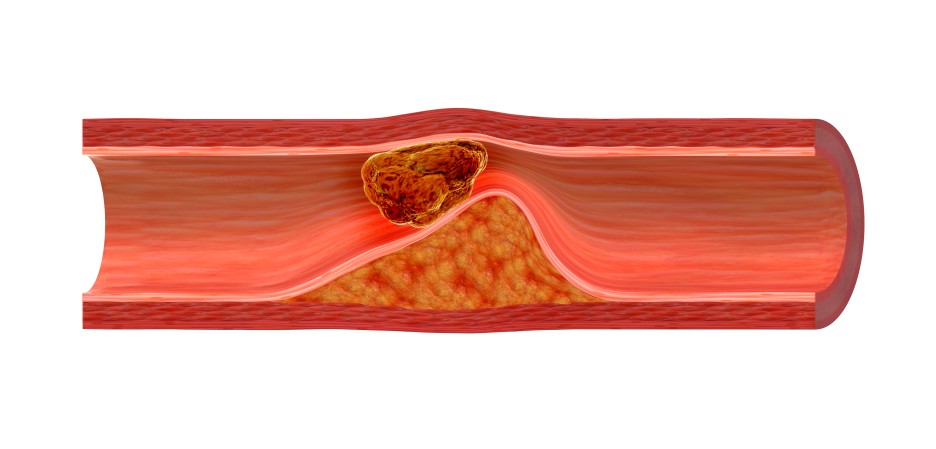

이처럼 지질이상증은 홀통혈관이 막힐 때까지 증상이 나타나지 않기 때문에

방치하는 경우가 많습니다.

이 질환을 방치하면 비만, 고혈압, 당뇨병 등은 물론

흐림이 막혀 동맥경화를 유발하고

심장 및 혈관질환을 일으킬 수 있습니다.

특히 고지혈증으로 인한 동맥경화는 혈관 내막에 노폐물이 쌓여 혈관 내경이 좁아져 혈류장애를 유발할 수 있습니다.

또한 동맥경화의 경우 특별한 증상이 나타나지 않으므로

동맥의 약 70% 이상이 막혔을 때 가끔 목덜미가 짜릿하거나 손이 떨리는 증상이 나오기도 합니다.

만약에 혈관이 심해져서 막히면

심근 경색이나 말초 동맥 질환 등의 합병증으로 이어질 수 있습니다.